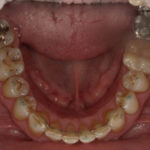

Arcade mandibulaire avant traitement orthodontique, séquelles de maladie parodontale

Après traitement orthodontique et réalisation d’une attelle fibrée (courtoisie Dr Patrick Fournier)